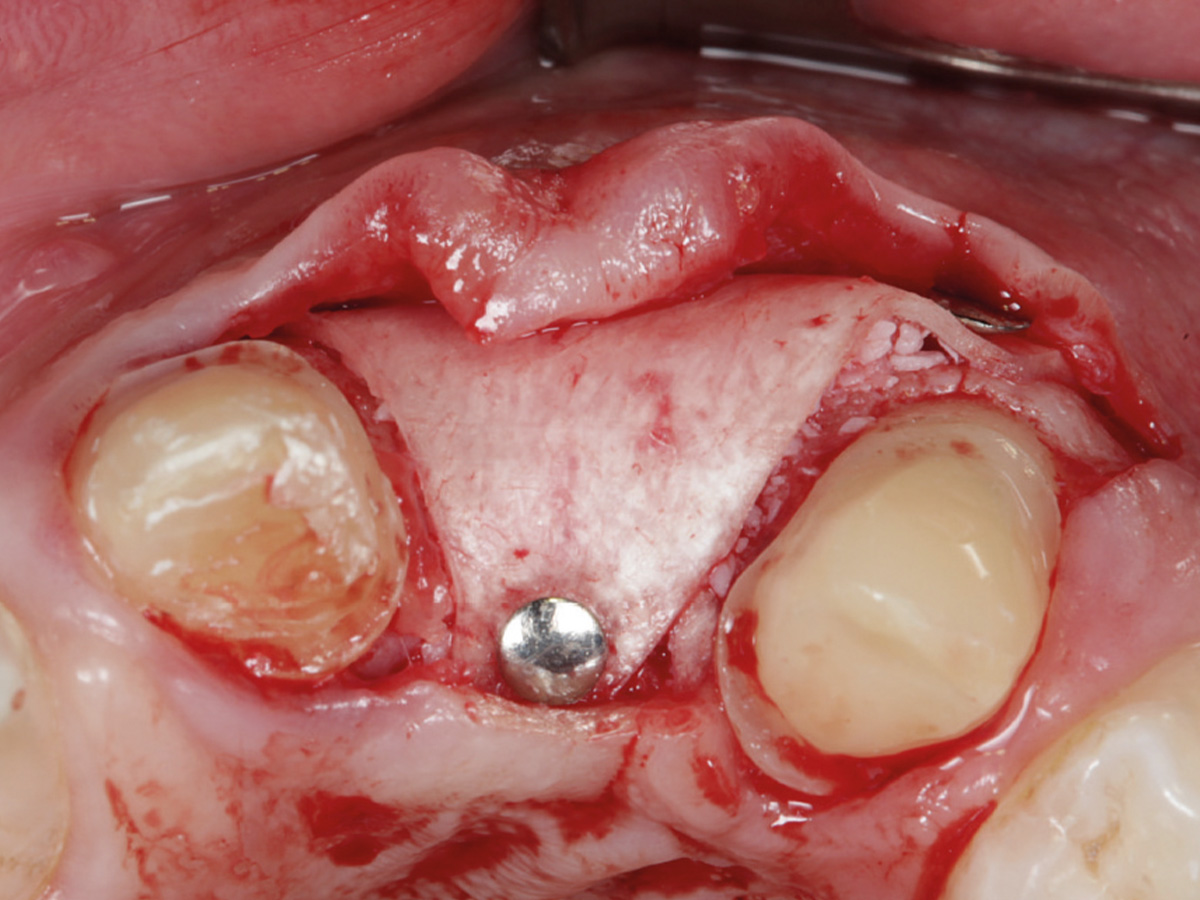

Abbildung 3

Nach Bildung eines Mukoperiostlappens wird mit der Bone Lamina die bukkale Lamelle rekonstruiert. Die Lamina wird mit Titanpins befestigt.